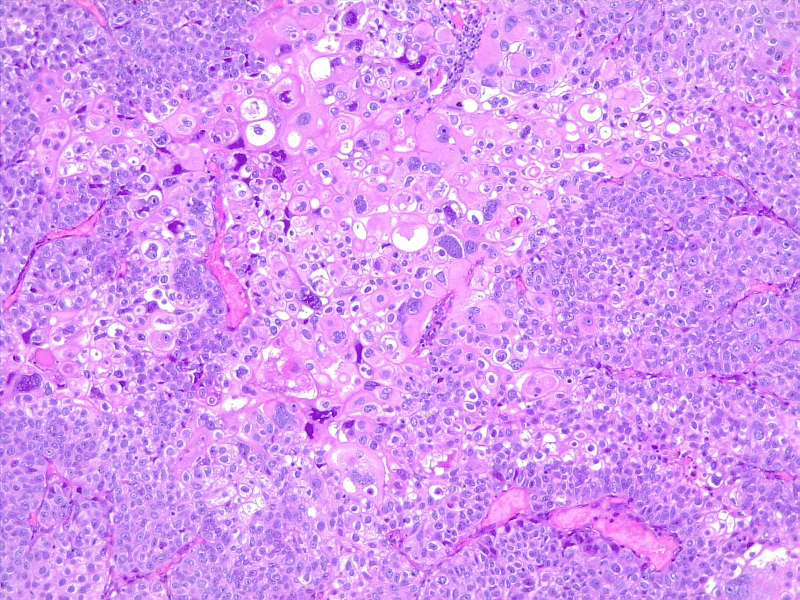

Bladder Cancer

圖1: 膀胱癌。圖片由 S Bhimji MD 提供